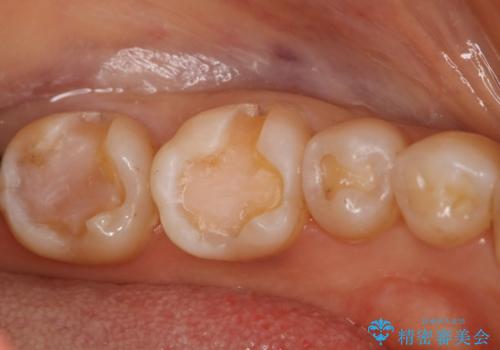

下の奥歯の銀歯を白くしたい

- 左下奥歯のメタルインレーを白くしたいと希望された患者様です。

形態、切削量などを考慮し、セラミックインレーにて治療を行いました。

メタルインレー、う蝕除去後にCRにて裏層した上で、形成・印象を行いました。